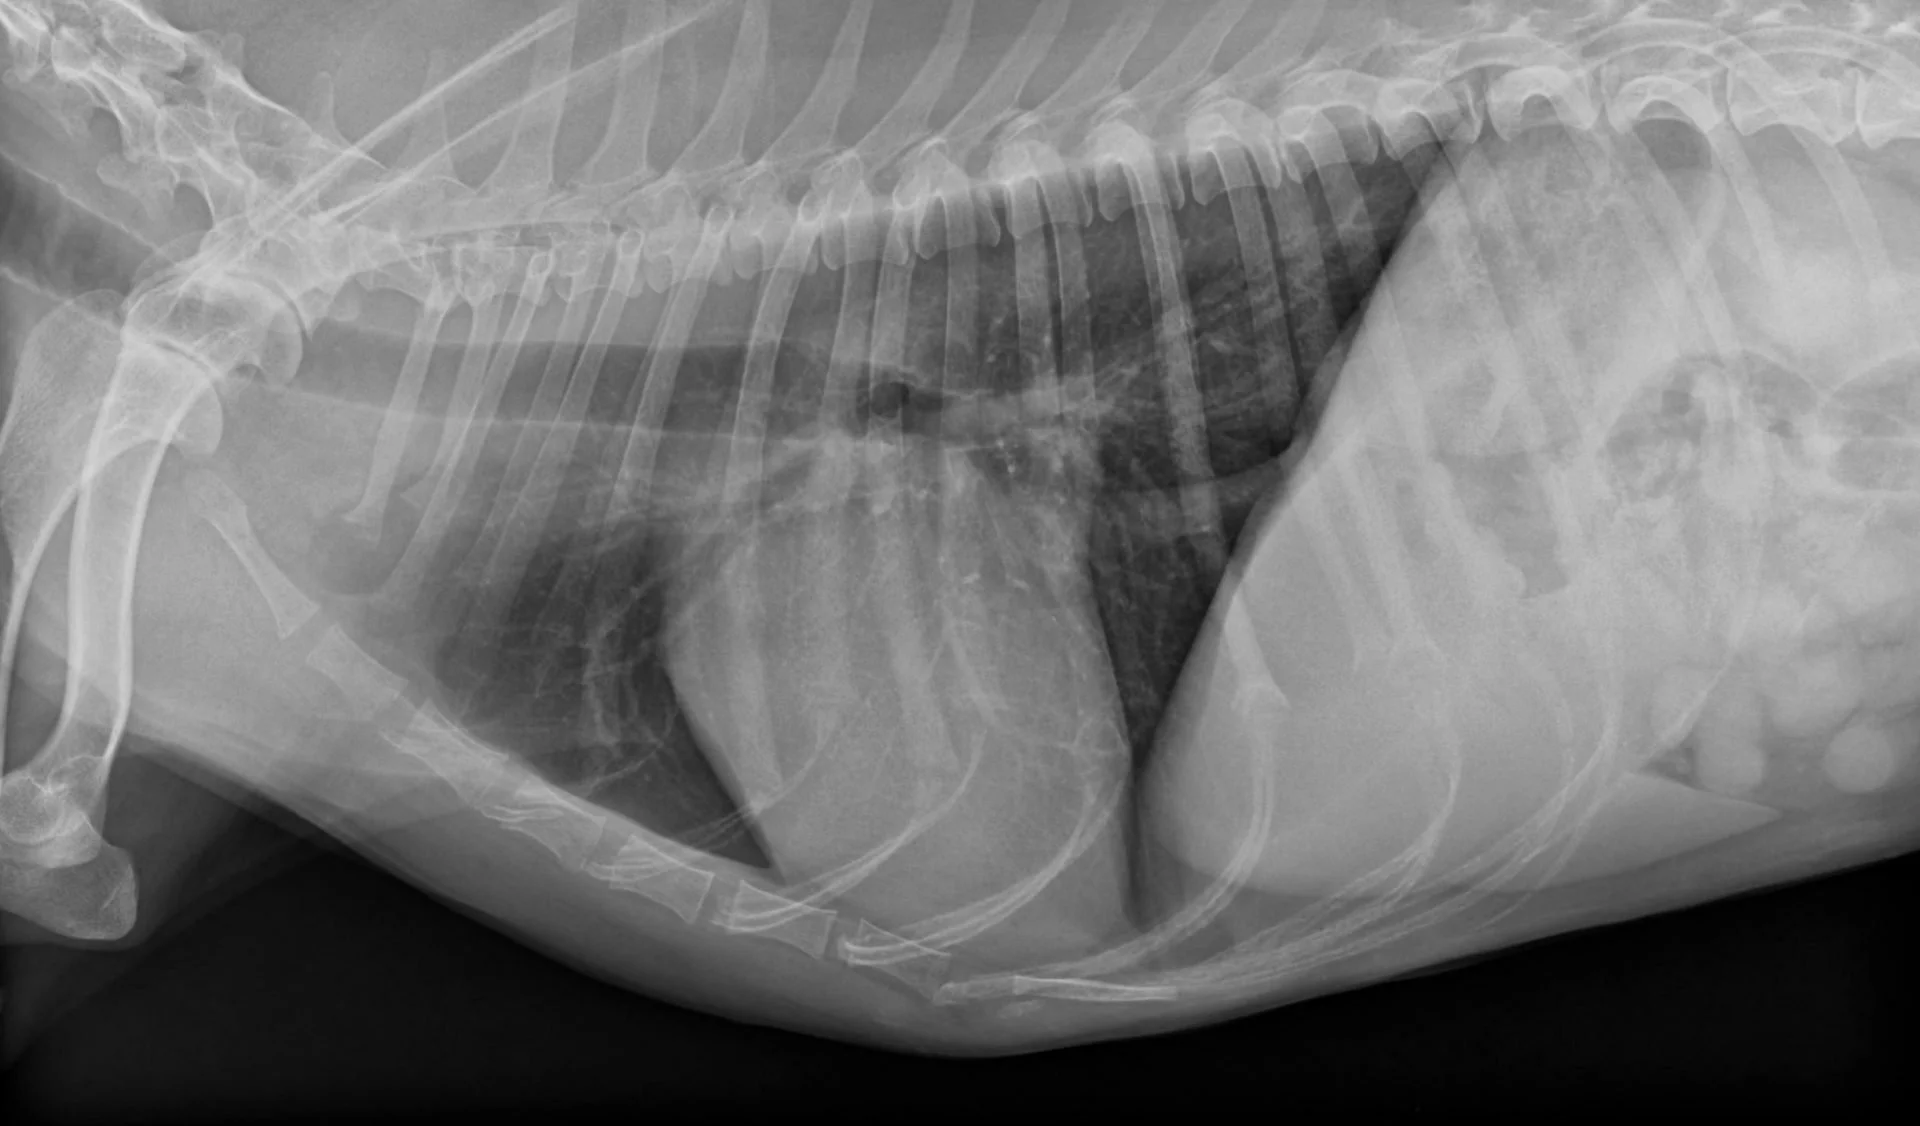

Röntgen

Die Strahlendiagnostik mittels Röntgen bei Tieren ist ein bildgebendes Verfahren, das Knochen, Gelenke und innere Organe sichtbar macht und so Diagnosen von Verletzungen oder Erkrankungen ermöglicht.

- Allgemeine röntgenologische Untersuchungen

- Hüftgelenksdysplasie (HD) mit offizieller Zulassung

- Ellbogendysplasie (ED)